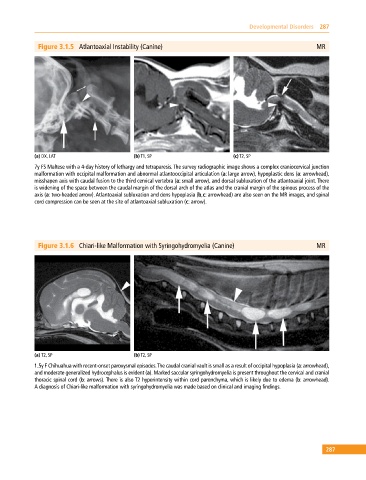

Figure 3.1.5 Atlantoaxial Instability (Canine) MR

(a) DX, LAT (b) T1, SP (c) T2, SP

7y FS Maltese with a 4‐day history of lethargy and tetraparesis. The survey radiographic image shows a complex craniocervical junction

malformation with occipital malformation and abnormal atlantooccipital articulation (a: large arrow), hypoplastic dens (a: arrowhead),

misshapen axis with caudal fusion to the third cervical vertebra (a: small arrow), and dorsal subluxation of the atlantoaxial joint. There

is widening of the space between the caudal margin of the dorsal arch of the atlas and the cranial margin of the spinous process of the

axis (a: two‐headed arrow). Atlantoaxial subluxation and dens hypoplasia (b,c: arrowhead) are also seen on the MR images, and spinal

cord compression can be seen at the site of atlantoaxial subluxation (c: arrow).

Figure 3.1.6 Chiari‐like Malformation with Syringohydromyelia (Canine) MR

(a) T2, SP (b) T2, SP

1.5y F Chihuahua with recent‐onset paroxysmal episodes. The caudal cranial vault is small as a result of occipital hypoplasia (a: arrowhead),

and moderate generalized hydrocephalus is evident (a). Marked saccular syringohydromyelia is present throughout the cervical and cranial

thoracic spinal cord (b: arrows). There is also T2 hyperintensity within cord parenchyma, which is likely due to edema (b: arrowhead).

A diagnosis of Chiari‐like malformation with syringohydromyelia was made based on clinical and imaging findings.